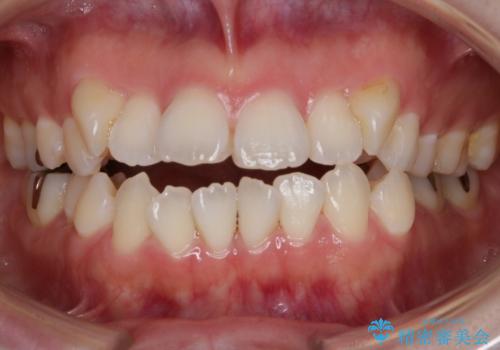

前歯のオープンバイト インビザラインで咬み合わせを改善